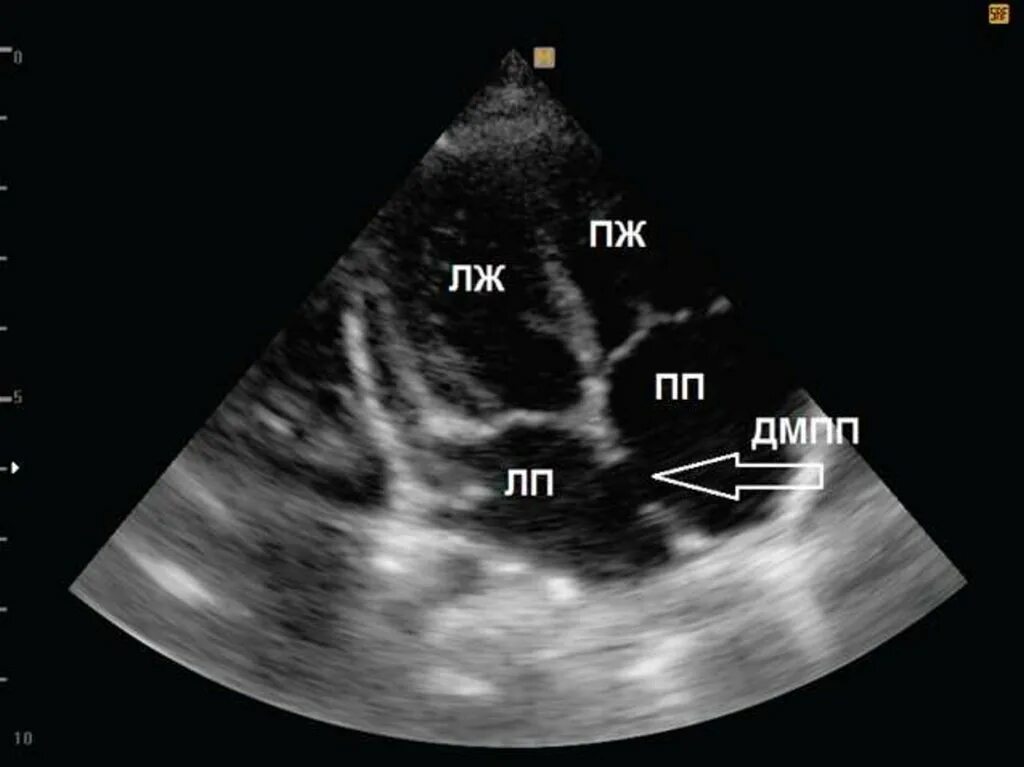

Аневризма мпп без